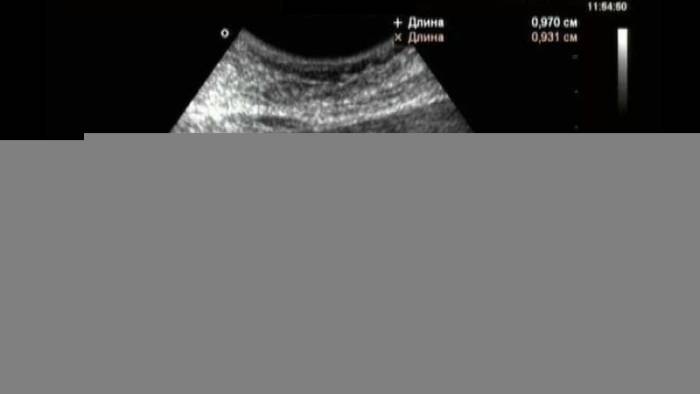

Гиперэхогенное образование щитовидной железы

Плохая экологическая обстановка, ионизирующее излучение, эндокринные заболевания, дефицит йода в организме и ряд других факторов могут вызвать гиперэхогенное образование щитовидной железы. В большинстве случаев уплотнение представляет собой узелок, который может разрастаться и делиться. Иногда даже повышенные стрессовые ситуации и наследственность провоцируют эхопозитивные включения.

Ткани щитовидки с повышенность плотностью могут быть связаны с такими состояниями: аденома железы, кальцинаты, папиллярный рак без инкапсуляции, хрящевые кольца трахеи и другое. Эхогенность не всегда проявляется на ранних этапах. Чаще всего патология дает о себе знать тогда, когда уплотнение достигает больших размеров.

Для уточнения причин новообразования и его вида, пациенту назначают комплекс всесторонних исследований. Кроме УЗИ необходимо сдать анализ на гормоны, общий анализ крови, рентген грудной клетки и многое другое. Если есть подозрения на онкологию, то показана тонкоигольная биопсия.

Лечение зависит от течения болезни, количества уплотнений, их размеров и особенностей организма больного. Если это единичный узелок менее 1 см, то назначается регулярное наблюдение у врача. Если узел доставляет дискомфорт, то для его лечения применяют различные методики подавления активности щитовидки. Это может быть лазерная деструкция, применение радиоактивного йода, этаноловая склеротерапия и другое. Хирургическое вмешательство возможно в том случае, если опухоль имеет большие размеры, вызывает болезненные ощущения и мешает дышать.